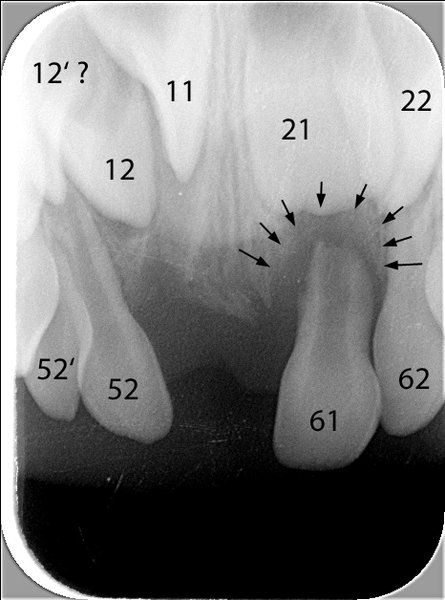

Anbei ein Fall einer 4½ Jahre alten Patientin, die Befunde in folgenden Bereichen aufzeigt: Unfallfolge mit Zahnverlust ( Punkt 1), überzählige Zähne (Punkte 2 und 3), Zahnstellungsabweichungen (Punkte 4 und 5).

- Vorzeitiger Verlust von zwei oberen mittleren Milch-Schneidezähnen infolge eines Sturzes (der rechte, 51, wurde direkt nach dem Sturz entfernt, der linke, 61, musste etwa 6 Monate danach entfernt werden, da sich im Knochen an der Wurzel eine Entzündung gebildet hatte). Beide Zähne sind auf dem klinischen Bild schon nicht mehr zu sehen. Die Entzündung im Knochen und die vorzeitige Auflösung der Wurzel des Zahnes 61 sind auf dem Röntgenbild 1 mit schwarzen Pfeilen markiert.

Dieses zeigt das Standard-Oberkiefer-Front-Röntgenbild, das gemacht wurde, um die Entzündung des linken mittleren Schneidezahnes darzustellen (schwarze Pfeile). Ebenfalls ist darauf zusehen, dass der Zahn 11 (mittlerer bleibender Schneidezahn) noch etwas «verdreht» im Knochen steht, sowie der vermutete überzählige Zahn 12'.

- Röntgenbild der Oberkiefer-Front mit Zahnbezeichnungen und Informationen